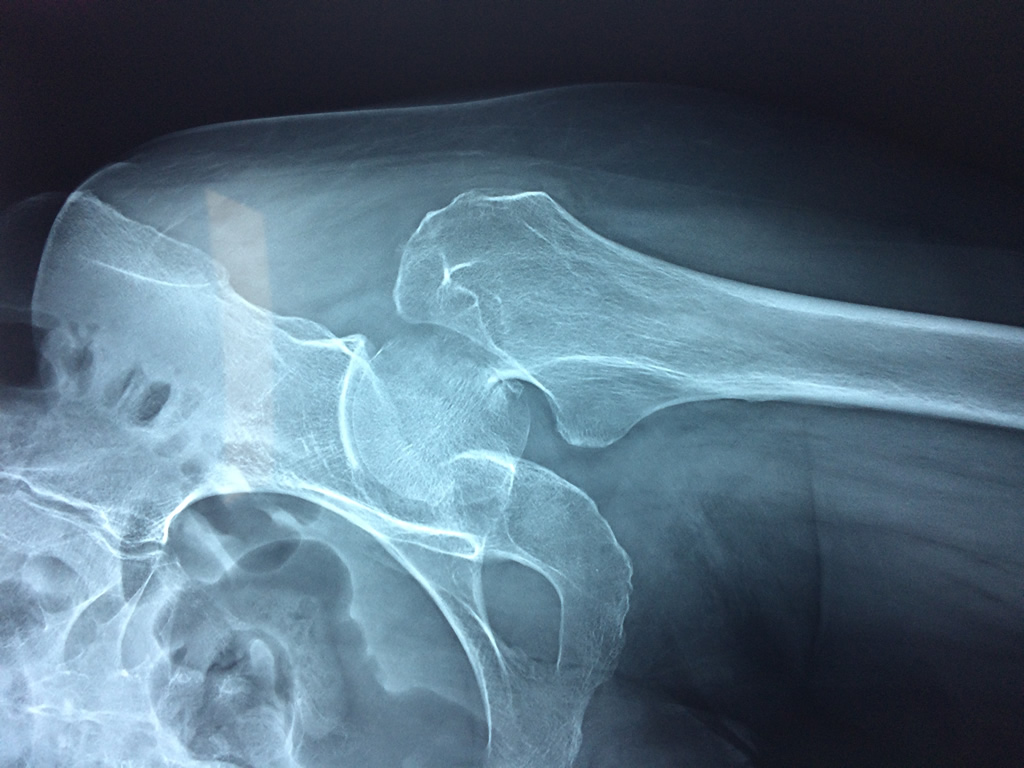

Cirugía de Fémur - Cadera

La cirugía de fractura de cadera se realiza para reparar una ruptura en la parte superior del hueso del muslo. Este hueso se denomina fémur.

Es parte de la articulación coxofemoral. Si una fractura de cadera no recibe tratamiento, es posible que deba permanecer en una silla o en la cama.